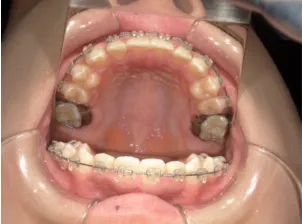

治療中➁小6:QH・BHでアーチ形態改善・上顎前歯を並べる

治療中③中1:非抜歯治療の診断で、上顎に歯の生えるスペースをつくるため上顎左右6をプレートで遠心移動し、隙間ができた時点